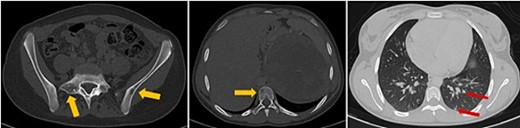

The patient underwent sonography followed by magnetic resonance imaging (MRI), which showed a large lobulated retroperitoneal left tumour measuring 20 × 16 × 14 cm, which was hypointense on T1-weighted and heterogenous on T2-weighted images with necrotic components and contrast-enhancing after Gadolinium administration. This mass invaded the left kidney, causing homolateral pelvicalyceal dilatation (Fig. 1). Routine staging for metastasis showed: lymph nodes and peritoneal carcinomatosis nodules, pulmonary nodules revealed on a thoraco-abdomino-pelvic computed tomography (CT) scans, and secondary-looking osteolytic lesions (Fig. 2) confirmed by scintigraphy.

Axial thoraco-abdominal CT image on the bone window showing lytic bone lesions of the left iliac wing, sacrum, and vertebral bodies and on the pulmonary window showing pulmonary nodules.